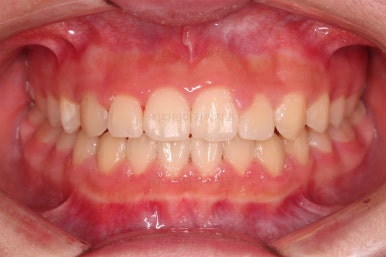

틈이 다 모였고 교합도 많이 좋아졌죠?

끝내도 될까요?

전후 사진을 비교해 볼게요.

악궁확장을 통해 위아래 악궁의 크기 조화를 맞췄고, 틈새도 모았으며 교합도 적절히 마무리를 했습니다.

웃는 모습도 훨씬 예뻐졌네요.

향후 유지관리가 다른 분들보다 훨씬 중요한 상황이라 볼 수 있겠습니다.